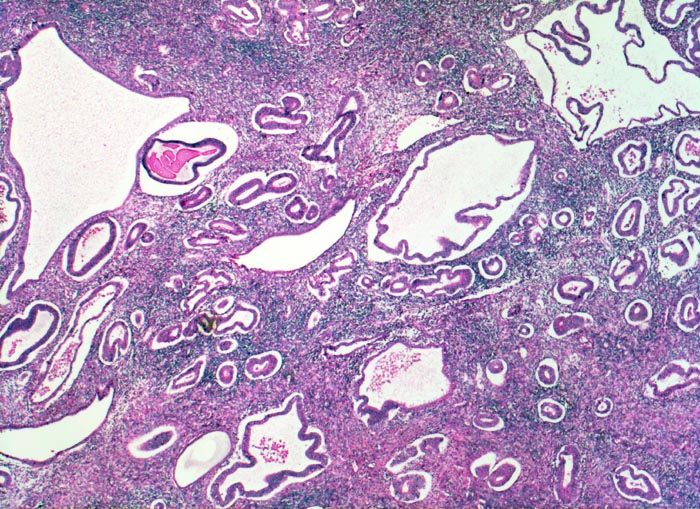

Einteilung der Endometriumhyperplasie nach WHO 2014:

• Hyperplasie ohne Atypie

• Hyperplasie mit Atypie (AH)/Endometrioide intraepitheliale Neoplasie (EIN) Die hyperplastische Mukosa ist verdickt (2-3cm statt normal 0.2-1.2cm), homogen-weisslich glasig und weich. Die Drüsen sind verstärkt verzweigt, zystisch transformiert und ausgekleidet von mehrreihigem Epithel. Bei der Hyperplasie beträgt das Drüsen-Stroma Flächenverhältnis >1:1. Die Vorstufe der Hyperplasie mit gleichartigen architektonischen Veränderungen aber einem Drüsen-Stromaverhältnis <1:1 bezeichnet man als unregelmässig proliferiertes Endometrium. 1-3% der Frauen mit einer Hyperplasie des Endometriums ohne Atypie entwickeln im Verlauf ein gut differenziertes endometrioides Adenokarzinom. Das Risiko für die Entwicklung eines endometrioiden Adenokarzinoms ist dagegen viel höher bei Vorliegen einer Hyperplasie mit Atypie (> 1074) (> 1075) oder einer endometrioiden intraepithelialen Neoplasie (=Präneoplasie) (> 10369). Bei einem Viertel bis einem Drittel der Patientinnen mit solchen Läsionen in der Kurettage wird in der nachfolgenden Hysterektomie oder innerhalb eines Jahres die Diagnose eines endometroiden Adenokarzinoms gestellt. Das Karzinomrisiko ist 14x erhöht bei der atypischen Hyperplasie bis 45x bei der EIN. In Einzelfällen kann die Abgrenzung einer atypischen Hyperplasie oder einer EIN von einem Karzinom am Kurettagematerial sehr schwierig sein. Beim invasiven Karzinom sind die Drüsenarchitekturstörungen ausgeprägter und zwischen den Karzinomdrüsen fehlt das Stroma stellenweise vollständig.

• Hoch aufgebaute Mukosa.

• Das Verhältnis von Stroma und Drüsen ist zu Gunsten der Drüsen verschoben (Drüsen:Stroma>1:1).

• Die architektonische Komplexität der Drüsen ist in den meisten Fragmenten gering. Viele Drüsen sind zystisch dilatiert oder verzweigt. Keine kribriformen Strukturen.

• Proliferierendes ein- oder mehrreihiges Epithel mit länglichen hellen Kernen und Mitosen.

• Einige Drüsen werden von metaplastischem tubarem Epithel oder Flimmerepithel ausgekleidet. Das sollte der Kliniker dem Pathologen mitteilen: